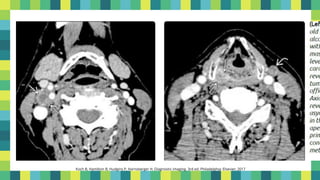

Imagen

▪ Evaluación pretratamiento

10

TAC

• (invasión cartílago

precisión general 75%

[S, E 84%])

RM

precisión general 78%

[S: 89-100%, E: 62%])

12

Koch B, Hamilton B, Hudgins P, Harnsberger H. Diagnostic imaging. 3rd ed. Philadelphia: Elsevier; 2017